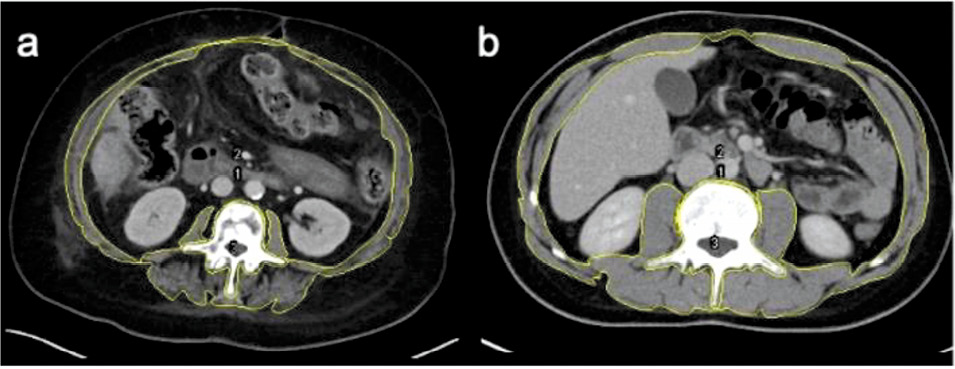

В настоящее время в клинической практике для диагнос- тики саркопении чаще всего используется метод КТ, позволяющий оценить площадь мышц и их качественное состояние. Для диагностики чаще всего выбирается уровень LIII позвонка (рис. 1). После контурирования (желтый цвет) внешнего (1) и внутреннего (2) периметров скелетной мышцы, а также III поясничного позвонка (3) площадь скелетных мышц можно рассчитать, используя математические уравнения. Показанные на рис. 1 анализируемые области являются показательными для пациента с низкой (а) и высокой (b) мышечной массой [19].

Рис. 1. КТ на уровне LIII позвонка (объяснение в тексте).

Fig. 1. CT scan at the level of the LIII vertebra (explanation in text).